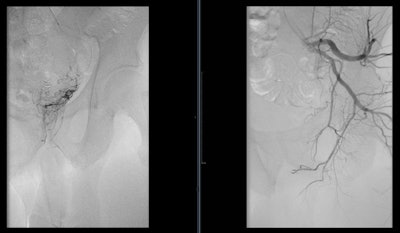

Angiogram of the left internal iliac artery showing the origin of the left prostatic artery and then very selective catheterization of the left prostatic artery by microcatheter.

Angiogram of the right internal iliac artery showing the origin of the right prostatic artery and then very selective catheterization of the right prostatic artery by microcatheter.How the treatment works